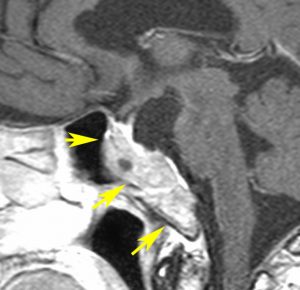

典型的なMRIの画像です

下垂体腺腫のMRIです。両側の視野障害(両耳側半盲)のために手術を受けた患者さんのものです。この腫瘍は非機能性腺腫といってホルモンを出さない腫瘍でした。少し大きめでしたが全部取れて視野の障害はよくなりました。

左の2枚はガドリニウム造影剤を使って写したもので腫瘍の形がよくわかります。右の1枚はT2強調画像と言います。MRIでは撮影の仕方によって見え方が違います。